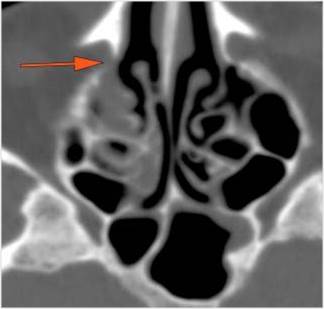

There is generalized mucoperiosteal thickening in the nasal cavity.

There is focal area of mucoperiosteal thickening or a destructive, ulcerative or necrotic abnormality of the nasal septum, turbinates or lateral walls of the nasal cavity.

There is infiltration in the posterior nasal cavity or sphenoethmoidal recess that is near to or protruding into the sphenopalatine foramen and pterygopalatine fossa.